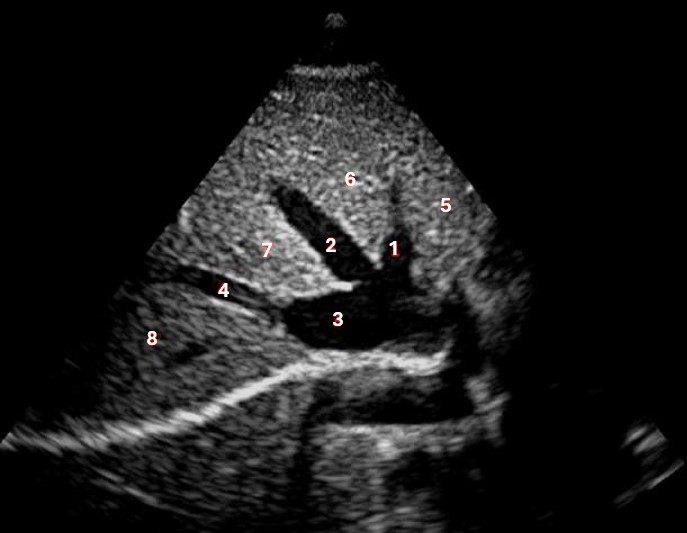

Which of the following structures is labeled number #1?

Left hepatic vein

Which of the following structures is labeled #2?

Middle hepatic vein

Which of the following structures is labeled #3?

IVC

Which of the following structures is labeled #4?

Right hepatic vein

Which structure/vessel is indicated by #5?

Lateral left lobe

Which of the following structures is labeled #8?

Posterior right lobe